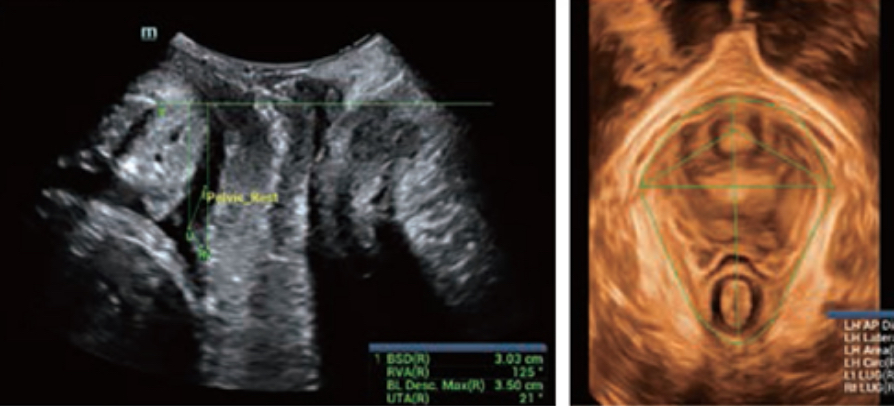

Realizing the increasing importance of ultrasound diagnosis on pelvic floor disorders, the new Resona 6 with Zone Intelligence provides a new solution to greatly simplify the operation procedures, and to minimize the exam time for a standardized evaluation on pelvic floor. With extremely simple user-interaction, it generates a standard coordinate system and automatically provides all related measurements within a few seconds.